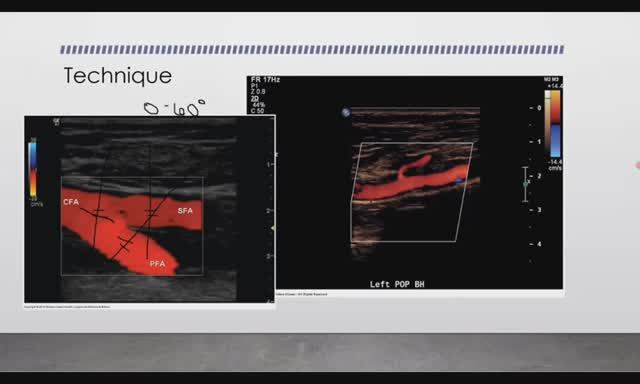

В этом видео более подробно разобрали УЗИ артерий нижней конечности, порядок проведения и заполнения протокола исследования. #узидгартерий #узиартерийнижнейконечности #узиартерий